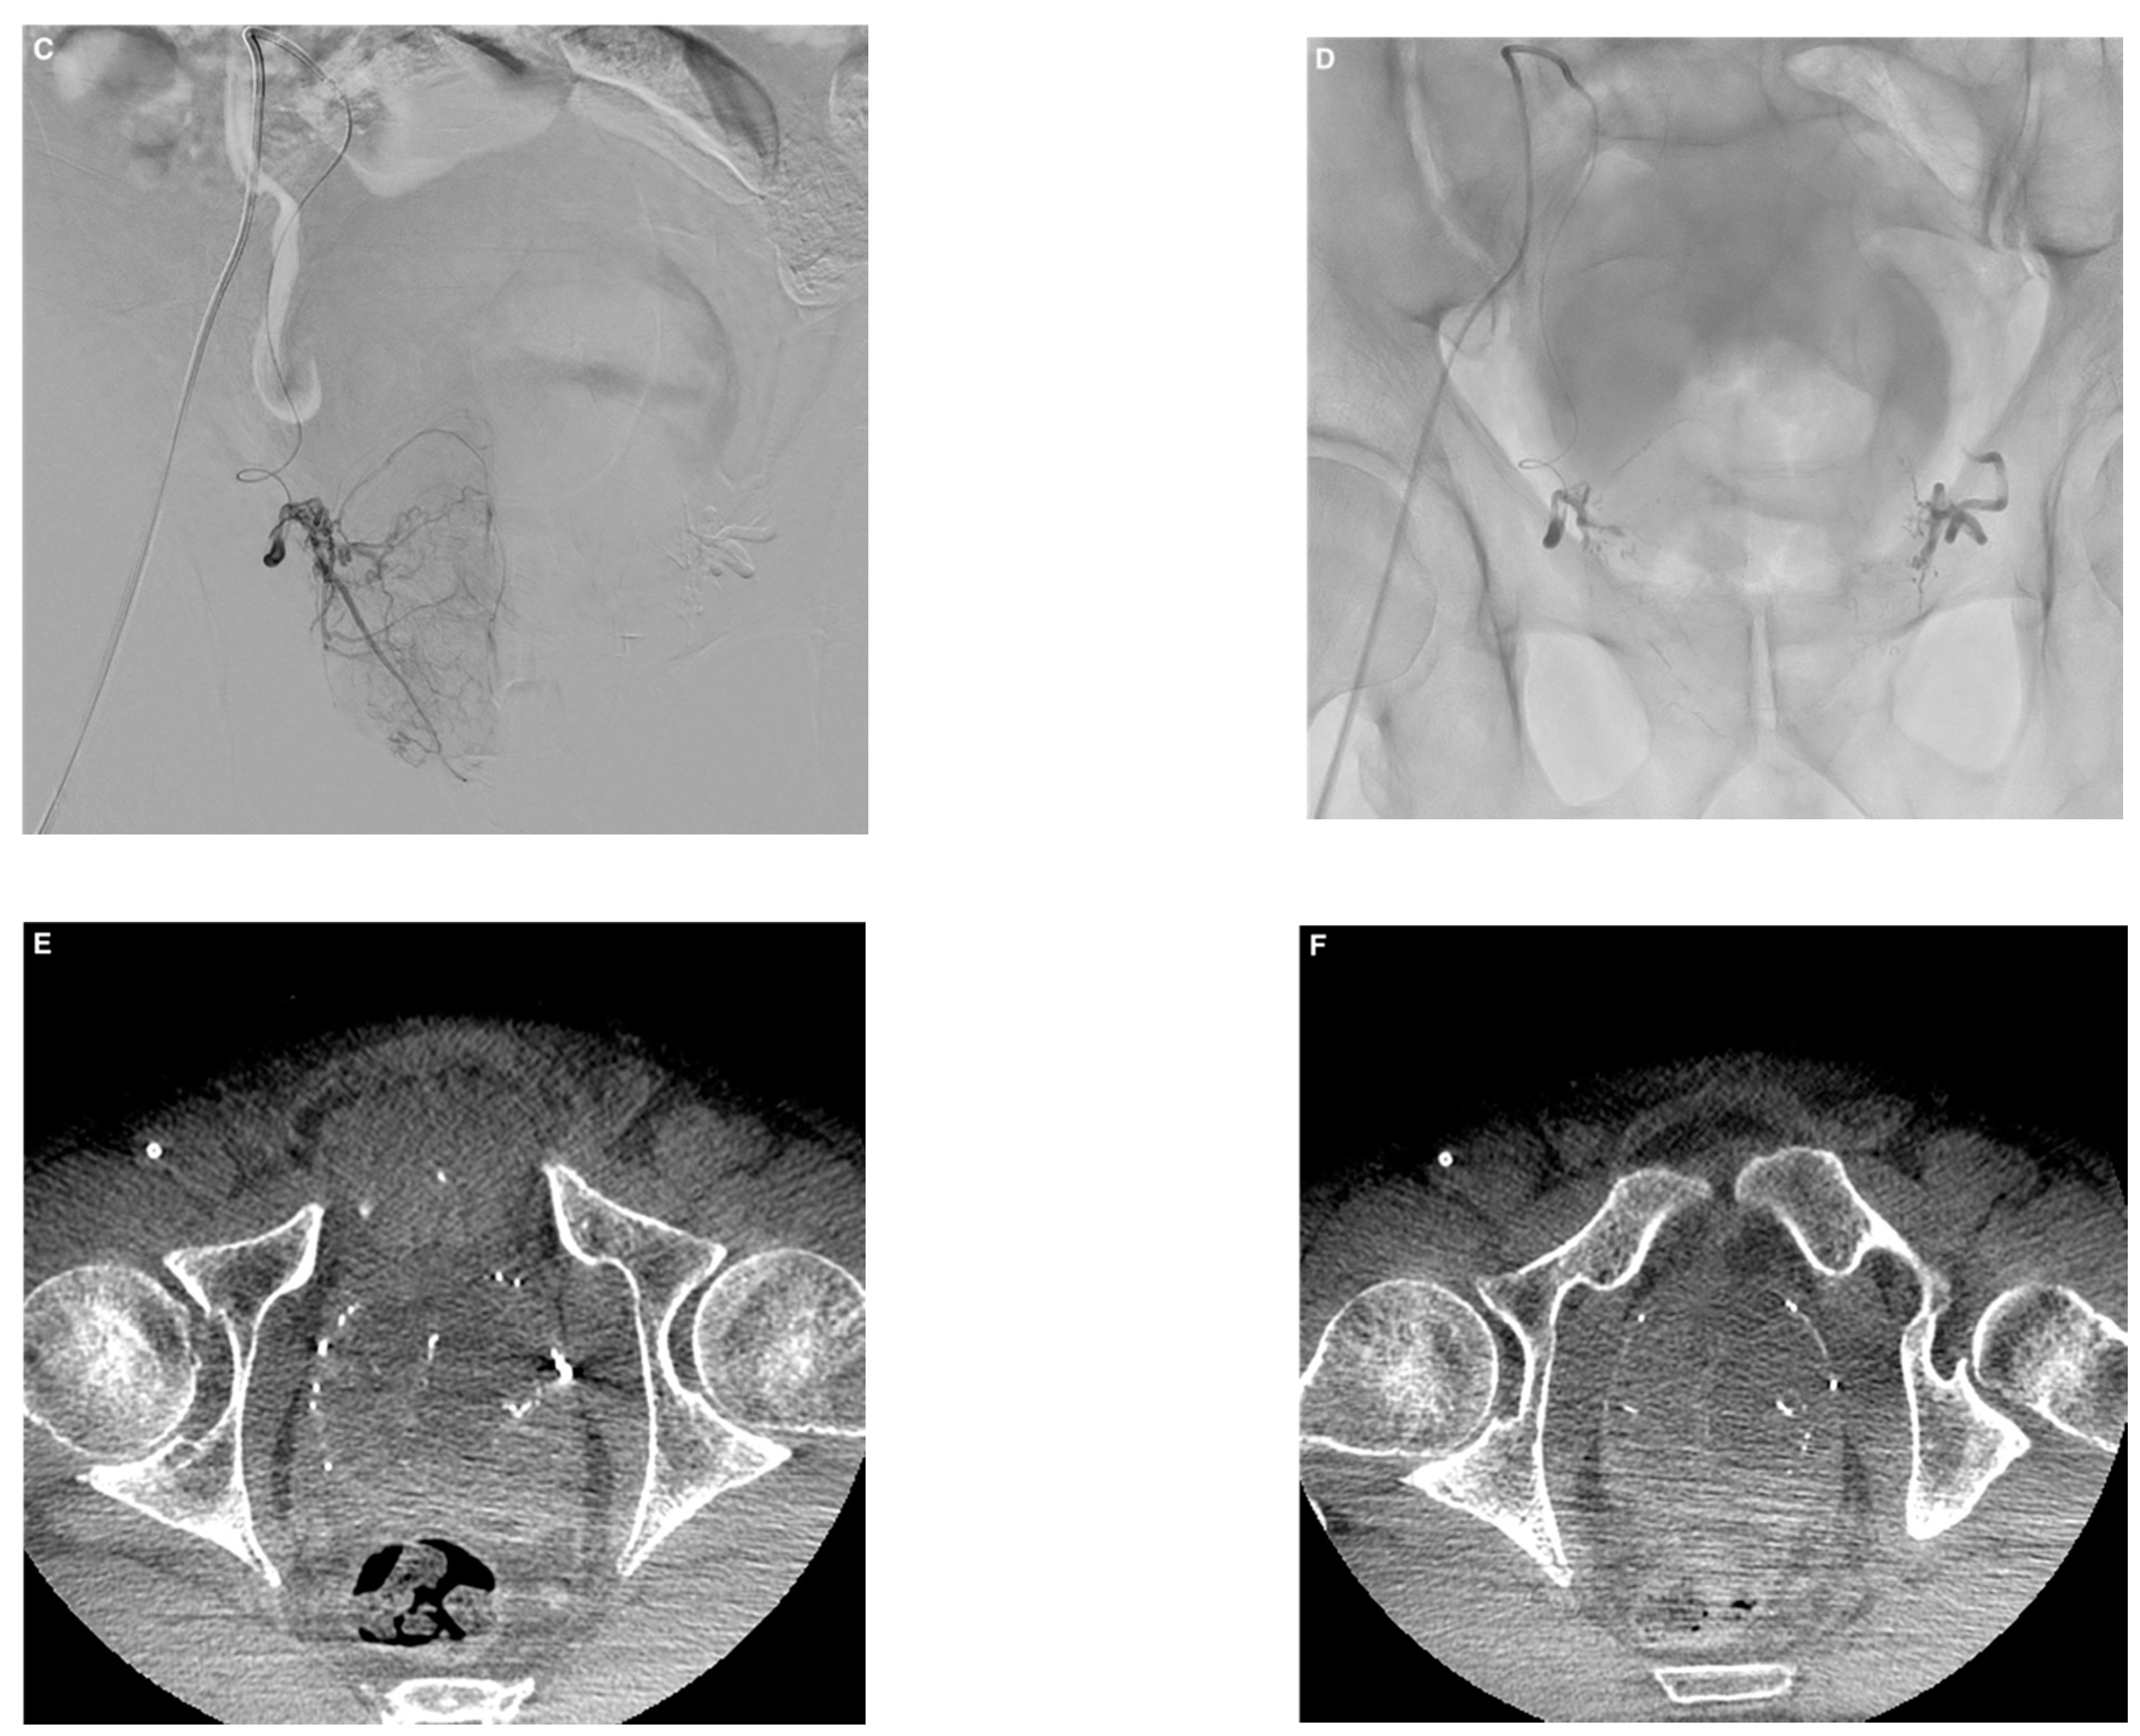

Embolization was performed according to established techniques, bilaterally in most cases (Figure 1) []. After microcatheter positioning within the feeding artery, 2 mg of isosorbide dinitrate (Risordan, 10 mg/10 mL vial) was administered intra-arterially on each side for vasodilation. The microcatheter dead space and vascular bed of the prostatic lobe were then abundantly flushed with 10 mL of 5% dextrose solution to prevent polymerization and promote distal embolization. NBCA glue (Glubran 2, GEM; Viareggio, Italy) was diluted with iodized oil (Lipiodol Ultra Fluid; Guerbet, Aulnay-sous-Bois, France) to make the material radiopaque. A homogeneous NBCA–Lipiodol mixture was prepared immediately before the injection using two 5 mL luer-lock syringes and a three-way stopcock. A high NBCA dilution of 1:8 was used to increase mixture fluidity, thereby allowing distal embolization. Embolization was performed in free or blocked flow. Effectiveness was assessed visually during PAE, and the injection was stopped when substantial reflux occurred. The microcatheter was then promptly removed.

Figure 1.

Example of prostate artery embolization (PAE) with N-butyl cyanoacrylate glue in a 74-year-old patient with symptomatic benign prostatic hyperplasia. (A) Left prostatic artery angiogram before PAE showing enhancement of the left prostatic lobe. (B) Follow-up angiogram after PAE with a mixture of Glubran®2/Lipiodol in a 1:8 ratio showing total occlusion. (C) Right prostatic artery angiogram with enhancement of the right prostatic lobe. (D) Visualization of the glue/lipiodol cast in the branches of the right prostatic artery after injection of the same mixture, with complete occlusion. (E,F) Axial cone-beam computed tomography images without contrast injection after bilateral PAE showing lipiodol uptake by both prostatic lobes with distal and proximal distribution of the glue/lipiodol casts. Major improvements in lower urinary tract symptoms were noted 3 months after PAE compared to baseline (IPSS, 5 versus 24; QoL score, 2 versus 6; prostate volume, 110 versus 170 mL).